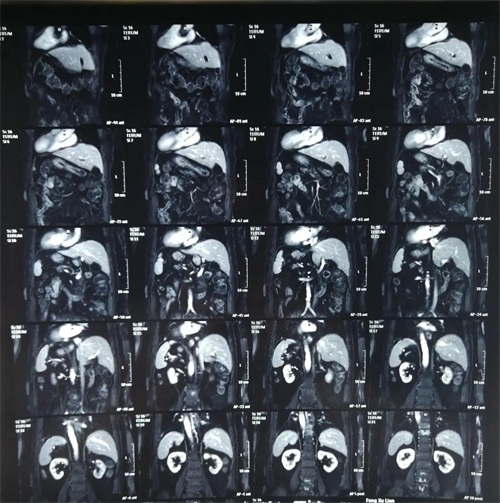

镜面人又称“镜子人”或“镜像人”,是一种极为少见的人体内脏解剖变异,指心、肺、横膈、肝、脾、胃、肠等全部内脏的位置呈180度反位,似正常人的镜面像,而循环、呼吸、消化功能均正常。 为“镜面人”做手术,极大地考验了术者的逆向思维能力,脏器的反位使取石手术难度和手术风险都增大。医生的手术习惯、技巧等也都要跟着一起“转位”。对病人来说,风险也在增大。给“镜面人”做手术,花费的时间远比正常人多。 近日我科收住一例腹腔内脏器反位病人,患者冯某某,年龄81岁,主因:右上腹间断性疼痛不适2月。入院诊断为:胆囊多发结石,急诊胆囊炎,主动脉硬化,三尖瓣反流,冠心病,心肌缺血,频发室性早博,同时合并有胸椎结核(T9-10)。患者年龄偏大,基础病多,手术风险大,行腹腔镜下胆囊切除术。